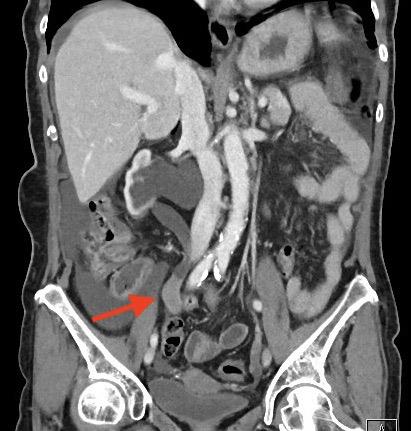

La urografía por tomografía computarizada (TC) – Uro TAC en nuestro país – es actualmente la técnica de imagen más precisa para el diagnóstico del CVUA, siendo de esta manera considerada como el estándar (Figuras 1 y 2)19. La TC puede ayudar además a predecir la etapa T del tumor primario (precisión hasta del 88%), siendo útil en la detección de metástasis regionales y a distancia (para esto último debe incluirse siempre una TC de Tórax)20. Sin embargo, presenta deficiencias en la detección de lesiones planas y tumores <3mm (hasta 40% de sensibilidad), casos en los cuales habitualmente es necesaria una evaluación endoscópica complementaria21. La TC con emisión de positrones (PET) constituye una alternativa promisoria para la evaluación de metástasis a distancia, con una sensibilidad superior a la TC convencional en estudios iniciales (85 vs. 50%), sin embargo requiere más validación para recomendar su uso rutinario en el estudio del CVUA22.

La técnica de URS flex para el diagnóstico de CVUA merece algunas consideraciones especiales (ver video adjunto). Cada vez que sea posible debería intentarse una inspección inicial “sin tocar” el uréter previamente. Es decir, sin introducir una guía hasta la pelvis renal antes de iniciar la ureteroscopía. Esto permite visualizar lesiones a lo largo de todo el uréter y en el sistema colector intrarrenal sin el artefacto o hemorragia que potencialmente pudiera causar la manipulación previa (Figura 3). Para acceder al tracto superior generalmente es necesario, eso sí, al menos dilatar el orificio ureteral y el uréter distal con un ureteroscopio semirrígido o un dilatador (secuencial, coaxial o balón) sobre una guía apenas insinuada. No existe evidencia suficiente para recomendar el uso rutinario de vaina de acceso ureteral, aunque ésta puede facilitar la toma de múltiples muestras para biopsia37.